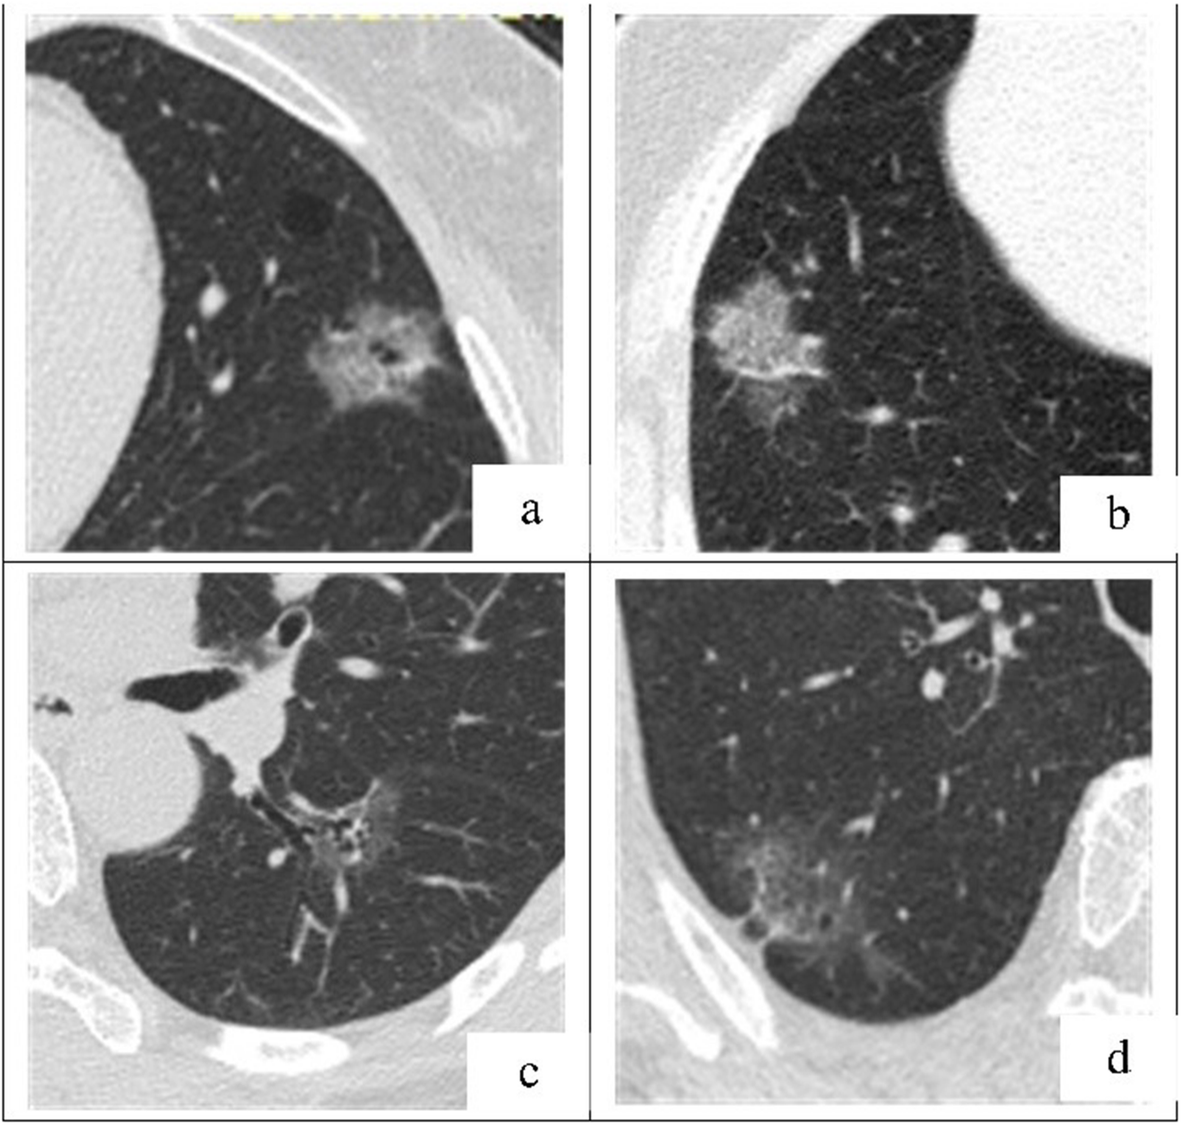

Fig. 3

a-d. Representative axial TSCT images of P-pGGNs in four patients, connected to the visceral pleural surface. The longer TLD, higher CT-LAP, lobulation signs and bubblelike-appearance suggest P-pGGN invasiveness. a A 63-year-old female with a P-pGGN in the left superior lobe, diagnosed as IAC, showed a 2.32 cm-TLD, lobulated, bubblelike-appearance, and − 467.31 HU-CT-LAP; b A 59-year-old female with a P-pGGN in the right superior lobe, diagnosed as IAC, showed a 3.09 cm-TLD lobulated and − 360.13 HU-CT-LAP; c A 57-year-old female with a P-pGGN in the left inferior lobe, diagnosed as MIA, showed a 2.36 cm-TLD, and − 630.43 HU-CT-LAP; d An 80-year-old female with a P-pGGN in the right superior lobe, diagnosed as MIA, showed a 4.16 cm-TLD, and − 662.7 HU-CT-LAP